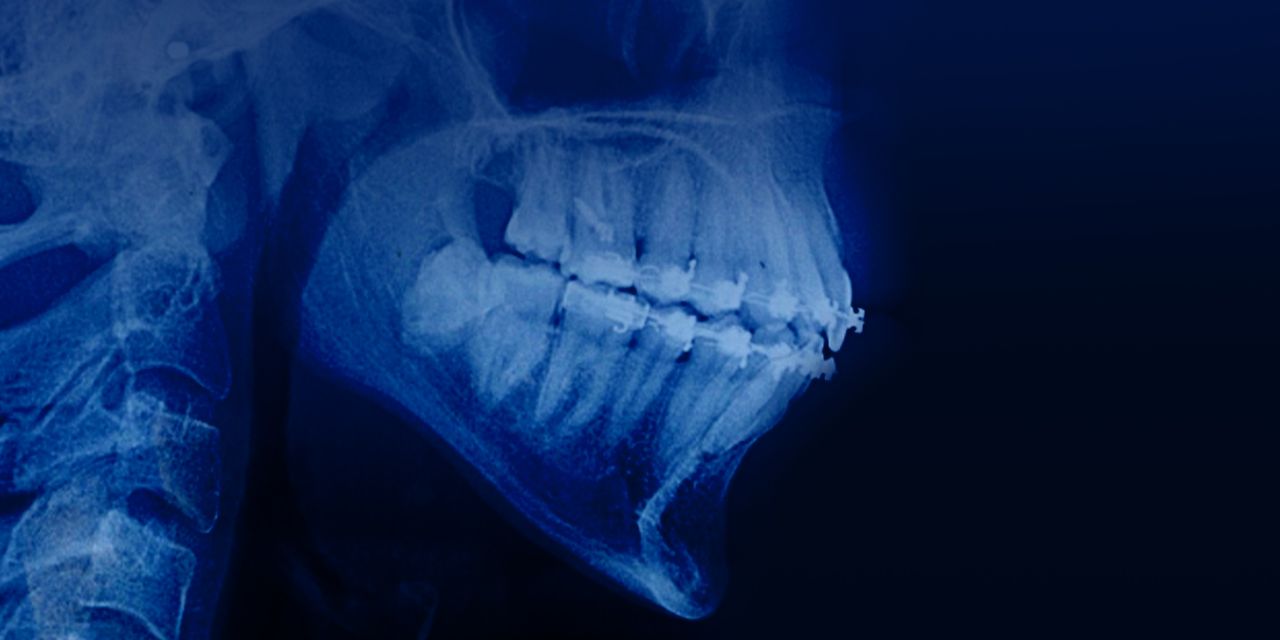

Manejo de pacientes adultos con mordidas abiertas y ángulo alto del plano mandibular

– Etiología del ángulo del plano mandibular alto y de las mordidas abiertas

– Diagnóstico del ángulo del plano mandibular alto y de las mordidas abiertas

– Perfil facial en el proceso de toma de decisión

– Inclusión del ángulo del plano mandibular en el proceso de toma de decisión

– Importancia del control vertical

– Determinación entre extracciones, extrusión de incisivos superiores/inferiores y/o intrusión del segmento posterior

– Indicaciones de extracción de dientes

– Diferencia entre la extracción del primer premolar, la segundo premolar o la extracción del primer molar

– Autorotación de la mandíbula

– Miniimplantes en el segmento posterior para la intrusión

– Indicaciones para la mecánica efectiva del arco de extrusión para la verdadera intrusión.